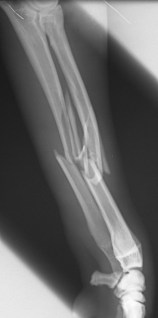

Συντριπτικό κάταγμα αντιβραχίου σε σκύλο από Πέτρος Μπεάκος08/01/201407/12/2017Σχολιάστε Προσθοπίσθια ακτινογραφία Πλάγια ακτινογραφία Οστεοσύνθεση κερκίδαςμε πλάκα και βίδες καιωλένης με ήλο και σύρμα Κοινοποιήστε: Στείλε ένα σύνδεσμο σε έναν φίλο(Ανοίγει σε νέο παράθυρο) Email Εκτύπωση(Ανοίγει σε νέο παράθυρο) Εκτύπωση Mοιραστείτε στο Facebook(Ανοίγει σε νέο παράθυρο) Facebook Μοιραστείτε στο X(Ανοίγει σε νέο παράθυρο) Χ Μου αρέσει! Φόρτωση... Σχετικά